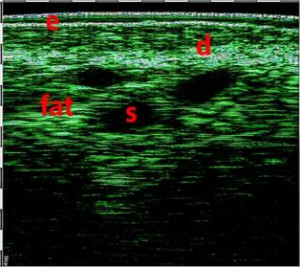

-Έγχυση Πληρωτικών Υλικών (Fillers)